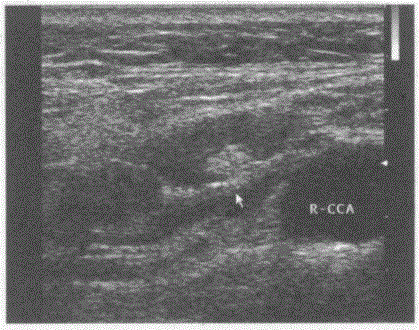

问题 临床资料:男,43岁,自述牙痛、嗓子痛。 超声综合描述:右颈总动脉旁可见数个长圆形低回声,边界清晰,形态规则,内回声不均,中部回声稍强,周边回声低。 超声提示:

选项 A.右颈部淋巴结结核 B.右颈部淋巴结转移瘤 C.右颈部正常淋巴结声像图 D.右颈部多发肿大淋巴结(慢性炎性肿大)

答案 D